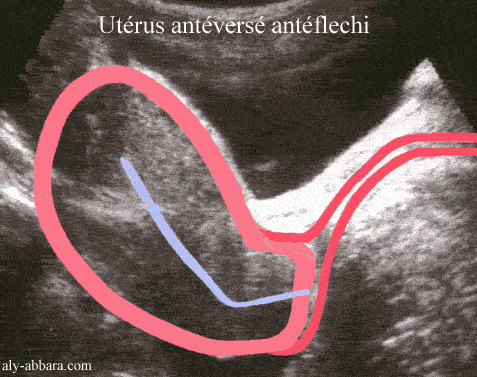

Utérus antéfléchi, antéversé

• On parle d'utérus antéfléchi quand l'angle qui se forme entre l'axe du col de l'utérus et l'axe du corps de l'utérus est ouvert en avant.

• On parle d'utérus antéversé quand l'angle que fait l'axe du corps de l'utérus avec un plan horizontal

passant par l'isthme est situé en avant de ce plan, donc le fond de l'utérus se situe à l'avant de ce plan.